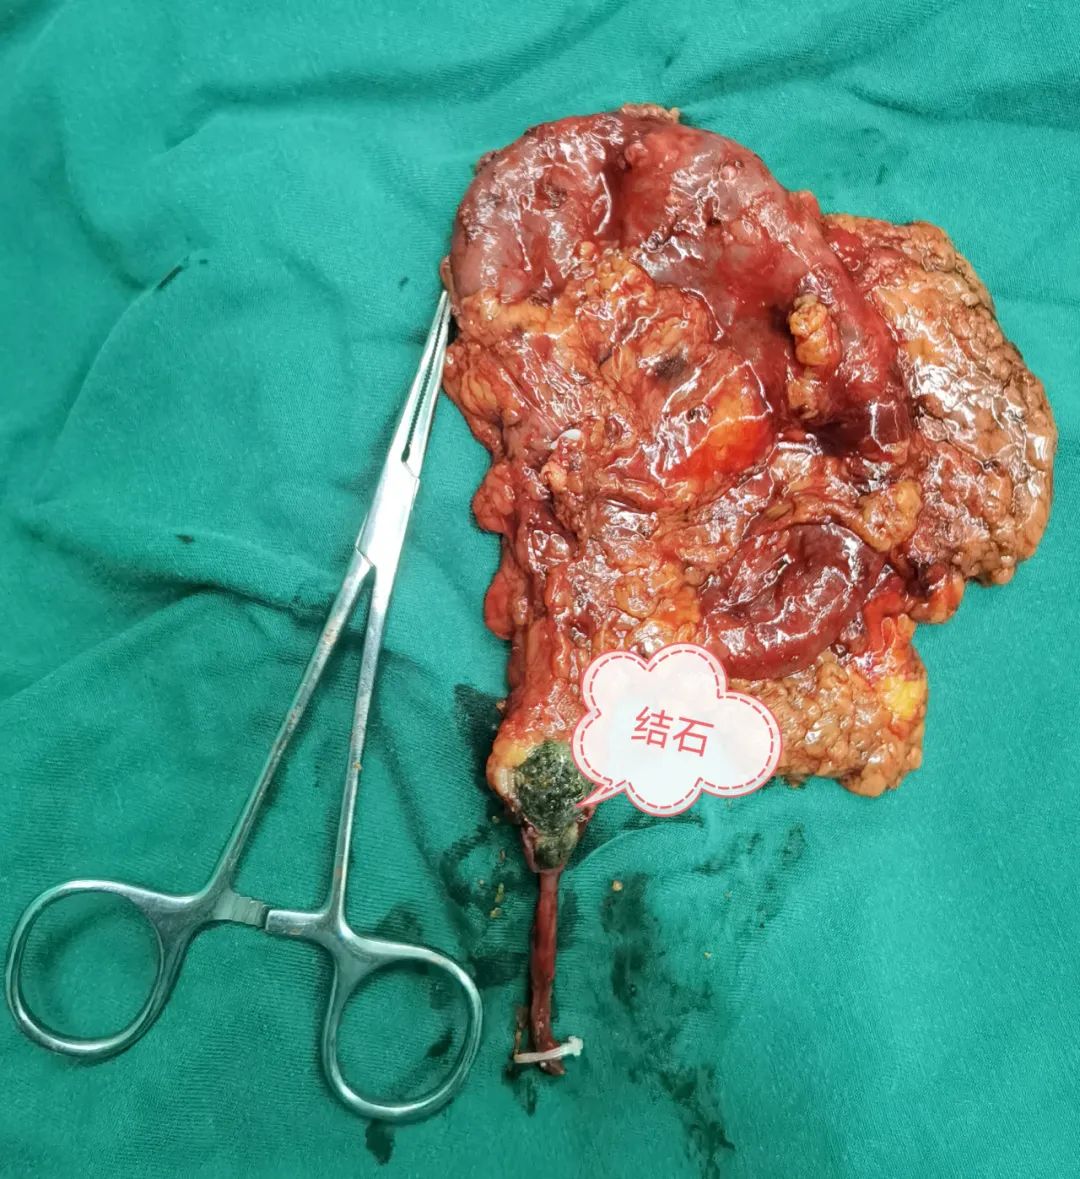

X光拍片显示杨大爷左侧输尿管有一2cmX1.2cm大小结石光影,在接下来的B超检查和增强CT检查中发现,杨大爷那颗卡在左侧输尿管的结石已经导致左肾萎缩失去了功能。 B超检查 CT检查 泌尿外科主任齐正华将检查结果告知杨大爷,提示他“左边的腰子保不住了,要切掉”。生性爽直幽默的杨大爷呵呵一笑:“既然没得用得了,割来甩了就是。” 心电图检查 在完善心电等术前相关检查后,10月27日上午,杨大爷被送进了手术室。泌尿外科主任齐正华和助手袁伟主治医师为杨大爷进行“腹腔镜下左侧无功能肾切除术+左肾周围粘连松解术”。 麻醉医师为手术提供保障 2个多小时全神贯注的手术 切除下的左肾 历时2小时40分,杨大爷萎缩无功能的左肾被成功取出,腹膜完整保留,整个过程出血量仅约10毫升。 泌尿外科主任医师杨胜云、主治医师袁伟检查杨大爷手术创口情况 经过几天的术后抗炎对症治疗,杨大爷尿量正常,各项指标无异常,于11月2日出院回家。 主治医师袁伟向杨大爷交待出院注意事项,杨大爷连连表示感谢。 专家提醒 泌尿外科主任、副主任医师齐正华提示:杨大爷本可保住这个肾的,由于早期结石形成的时候没有引起足够的重视,导致肾积水发生,积水时间一长就影响到肾功能,最终导致肾功衰肾萎缩。 齐正华说,临床上这类病例有很多,都跟杨大爷一样,早期往往仅出现腰胀腰痛等症状,因为还能耐受得住,所以大多数的患者都不会往尿路结石方面去想。 齐主任温馨提醒各位结石患者及朋友们,平时要多饮水,定期到正规医院进行健康检查,早发现,早治疗,别让“时间”成为了我们一辈子的遗憾。 泌尿外科专科门诊:新门诊综合楼二楼212诊室。 特需专家门诊:每周四上午,新门诊综合楼一楼113诊室。 泌尿外科住院部:住院综合大楼五楼。 咨询电话:0830-5266595